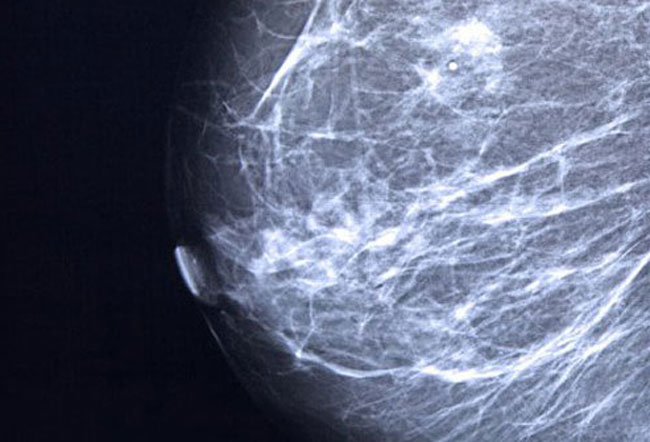

1 ) ماموگرافی

ماموگرافی نوعی روش پرتونگاری است که می تواند برای تشخیص سرطان پستان در مراحل اولیه بسیار مفید باشد.در این روش ، سینه ها در بین دو سطح ثابت قرار گرفته و برای برسی کامل بافت سینه ، کمی فشار داده می شوند.سپس توسط اشعه ایکس ، تصاویر سیاه و سفید از بافت سینه تهیه می شود.توصیه می شود زنان بعد از سن 45 سالگی ، سالی یکبار ماموگرافی انجام دهند.بعد از 54 سالگی بهتر است سالی دوبار انجام شود.